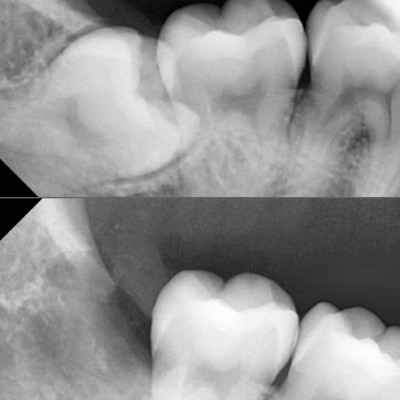

#38,48 사랑니 발치 #38,48 사랑니 발치 구강 외과 전문의가 당일발치했습니다.

작성자 이턱이 작성일 01-19 조회 46